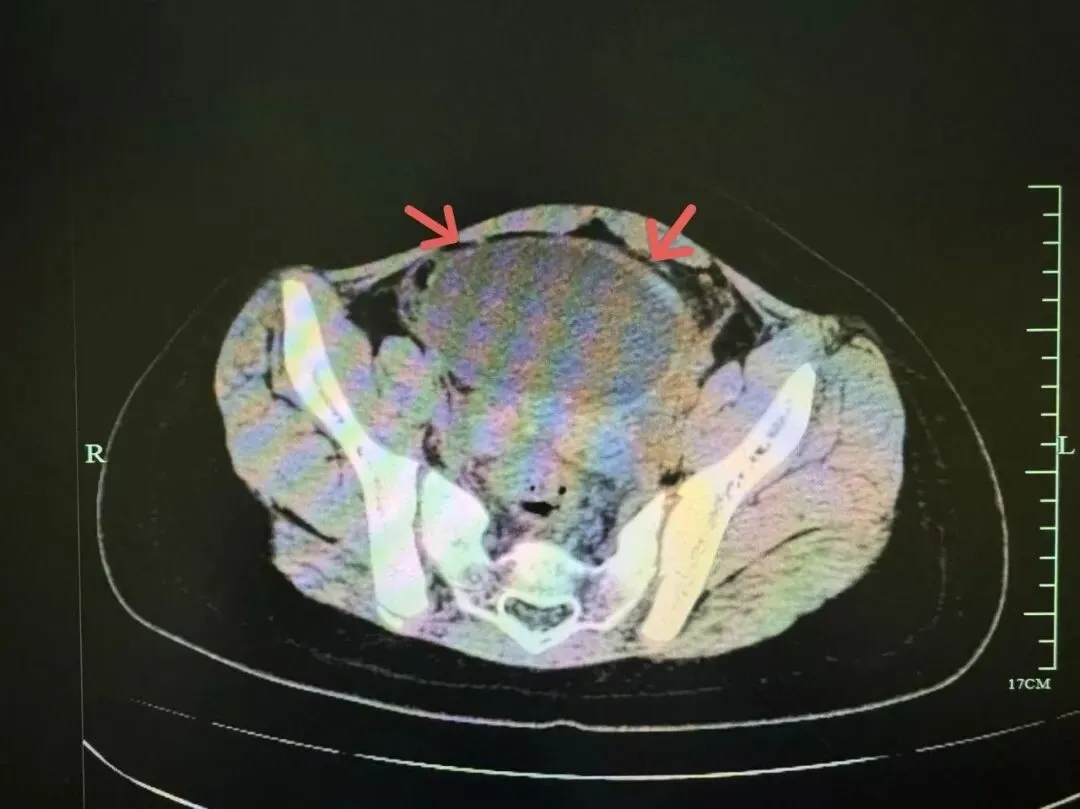

根据B超和CT显示,小吉的盆腔内有一个约9.5cm的巨大卵巢囊肿,并且已发生了“蒂扭转”,这是一种需要紧急手术的妇科急腹症!浙江省中西医结合医院儿科主任詹璐告诉记者,“这个囊肿以前可能就有,那段时间小吉的学校里要每天做仰卧起坐,造成这个囊肿一点点扭过去了。”